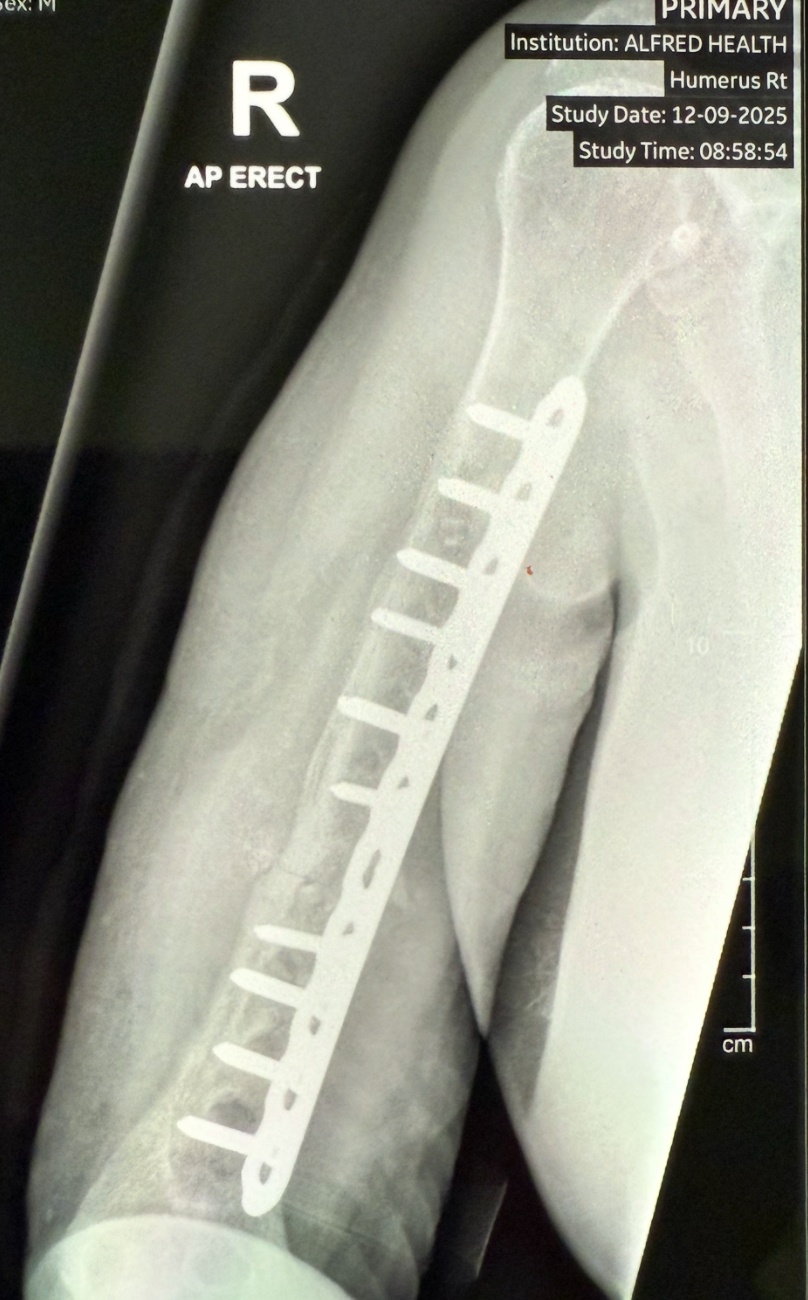

Michael's Arm - update 191125

The surgery was a great success and the arm is back in one piece again. Dr Raf Aasid from the RSPCA said the surgery could not have gone any better and Michael will be back wanking other blokes with his right hand in no time.